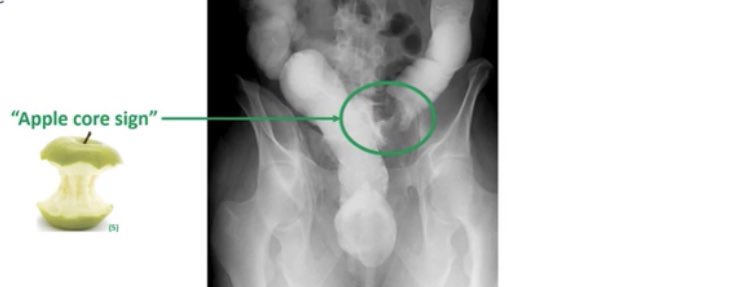

⚪️Apple 🍎 Core Sign➡️ indicates Colon CA

✳️Know that‼️:

Right side Colon CA usually present with anemia and left present with Bowel obstruction